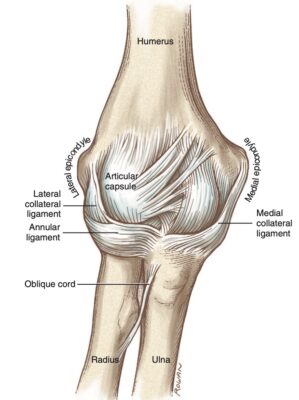

- Dây chằng bên trong , hay dây chằng bên trụ, bao gồm ba phần: đoạn trước, sau và ngang. Bó trước là thành phần mạnh nhất và nổi rõ nhất, trong khi bó sau là sự dày lên của phần sau của bao khớp và cung cấp sự ổn định ở góc gập 90 độ.

- Phức hợp dây chằng bên ngoài bao gồm dây chằng bên quay, dây chằng vòng quay (annular ligament), và dây chằng bên trụ ngoài (lateral ulnar collateral ligament). Dây chằng bên trụ ngoài đóng góp nhiều nhất vào sự ổn định ở mặt ngoài của khớp khuỷu. Tổn thương cấu trúc này có thể dẫn đến mất vững xoay sau ngoài.

- Các thành phần làm vững chính của khớp khuỷu bao gồm khớp cánh tay trụ, dải trước của dây chằng bên trong, và dây chằng bên trụ ngoài.

- Dây chằng bên trụ rất quan trọng bảo vệ bên trong, phòng ngừa dạng khuỷu khi bị lực tác động trong các hoạt động. Nhiều môn thể thao tiếp xúc và hoạt động gây sức ép lên mặt trong khớp, gây chấn thương.

- Dây chằng bên quay làm vững bên ngoài và ít khi bị chấn thương.

- Dây chằng vòng quay ôm quanh chỏm xương quay để giữ vững.